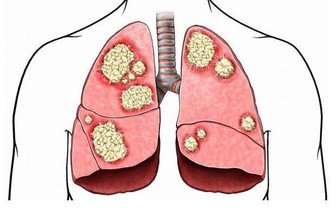

3.大腦因素:所有神經均來源於大腦, 當腦部出問題. 如中風, 則大腦所支配區會出現麻木, 無力.

4.全身因素:一些全身的疾病如:

A. 血脂過高: 長期血脂過高, 易引起血管壁硬化, 加上血脂過高, 血液粘稠, 血流變慢, 細胞所得到氧氣養料減少,導致麻木.

B. 糖尿病人: 血糖維持較高水平, 長久以往, 對人體血管, 神經造成極大傷害, 血管硬化, 神經變性.